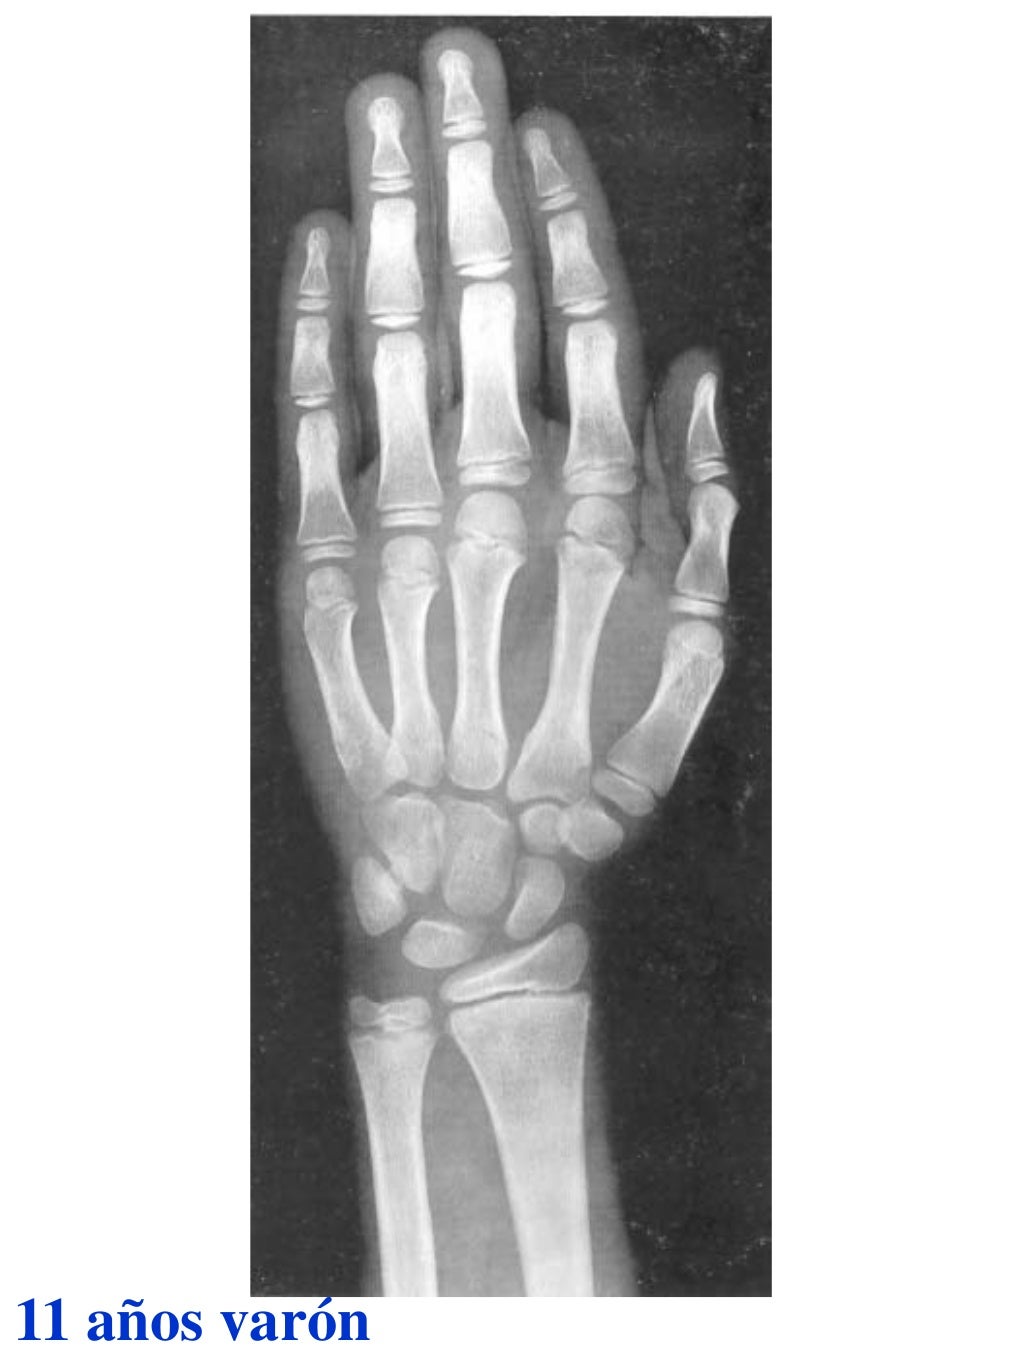

Tablas De Greulich Y Pyle The standards established by greulich and pyle, undoubtedly the most popular method, consist of two series of standard plates. The standards established by greulich and pyle, undoubtedly the most popular method, consist of two series of standard plates. El documento lista las edades. This systematic review summarizes the. The greulich and pyle method is one of the two main ways to assess the bone age of children. Both main methods of bone age. Scribd is the world's largest social reading and publishing site. 153 recomendaciones • 616,869 vistas. Atlas greulich y pyle | pdf | descarga gratuita. The greulich and pyle atlas is used to estimate the age of children and adolescents. The radiographic atlas of skeletal development of the hand and wrist by ww greulich and si pyle is a classic radiological.

Atlas greulich y pyle Tablas De Greulich Y Pyle The standards established by greulich and pyle, undoubtedly the most popular method, consist of two series of standard plates. Atlas greulich y pyle | pdf | descarga gratuita. Scribd is the world's largest social reading and publishing site. 153 recomendaciones • 616,869 vistas. The radiographic atlas of skeletal development of the hand and wrist by ww greulich and si pyle. Tablas De Greulich Y Pyle.

Atlas greulich y pyle Tablas De Greulich Y Pyle Both main methods of bone age. 153 recomendaciones • 616,869 vistas. The greulich and pyle method is one of the two main ways to assess the bone age of children. The standards established by greulich and pyle, undoubtedly the most popular method, consist of two series of standard plates. Scribd is the world's largest social reading and publishing site. This. Tablas De Greulich Y Pyle.